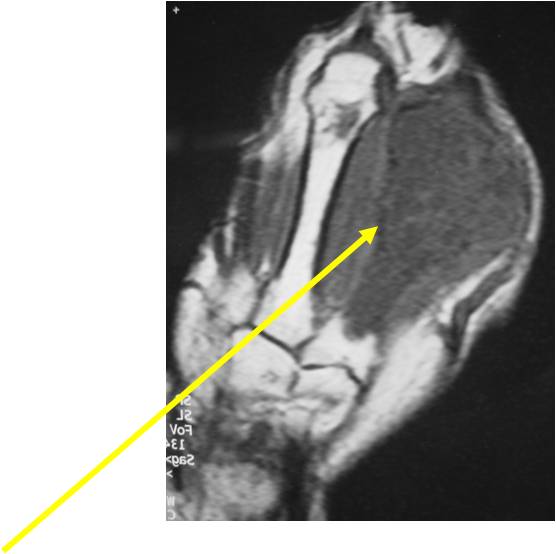

- MRI

- Lobulated margin

- Marked increased intensity long TR images

MRI:

- Lobulated margin (Lobular Growth Pattern)

- T2 Weighted Images: High Signal Intensity

- High water content shows as high signal on T2 weighted images

- Calcifications will be low signal

- Calcified chondroid – low intensity all sequences

- There should never be any cortical destruction nor a soft tissue component. If this exists then the tumor must be a chondrosarcoma.

- Endosteal scalloping and cortical expansion is acceptable for phalangeal tumors. In most benign long bone cartilage tumors there is minimal endosteal scalloping but there should be no cortical expansion nor thickening. There should be no cortical destruction and no soft tissue component associated with an enchondroma. Cortical destruction, periosteal thickening, cortical expansion and a soft tissue component indicates a chondrosarcoma of the long bone.

T2: High Signal No Soft Tissue Component

T1: Intermediate Signal Lobular Growth